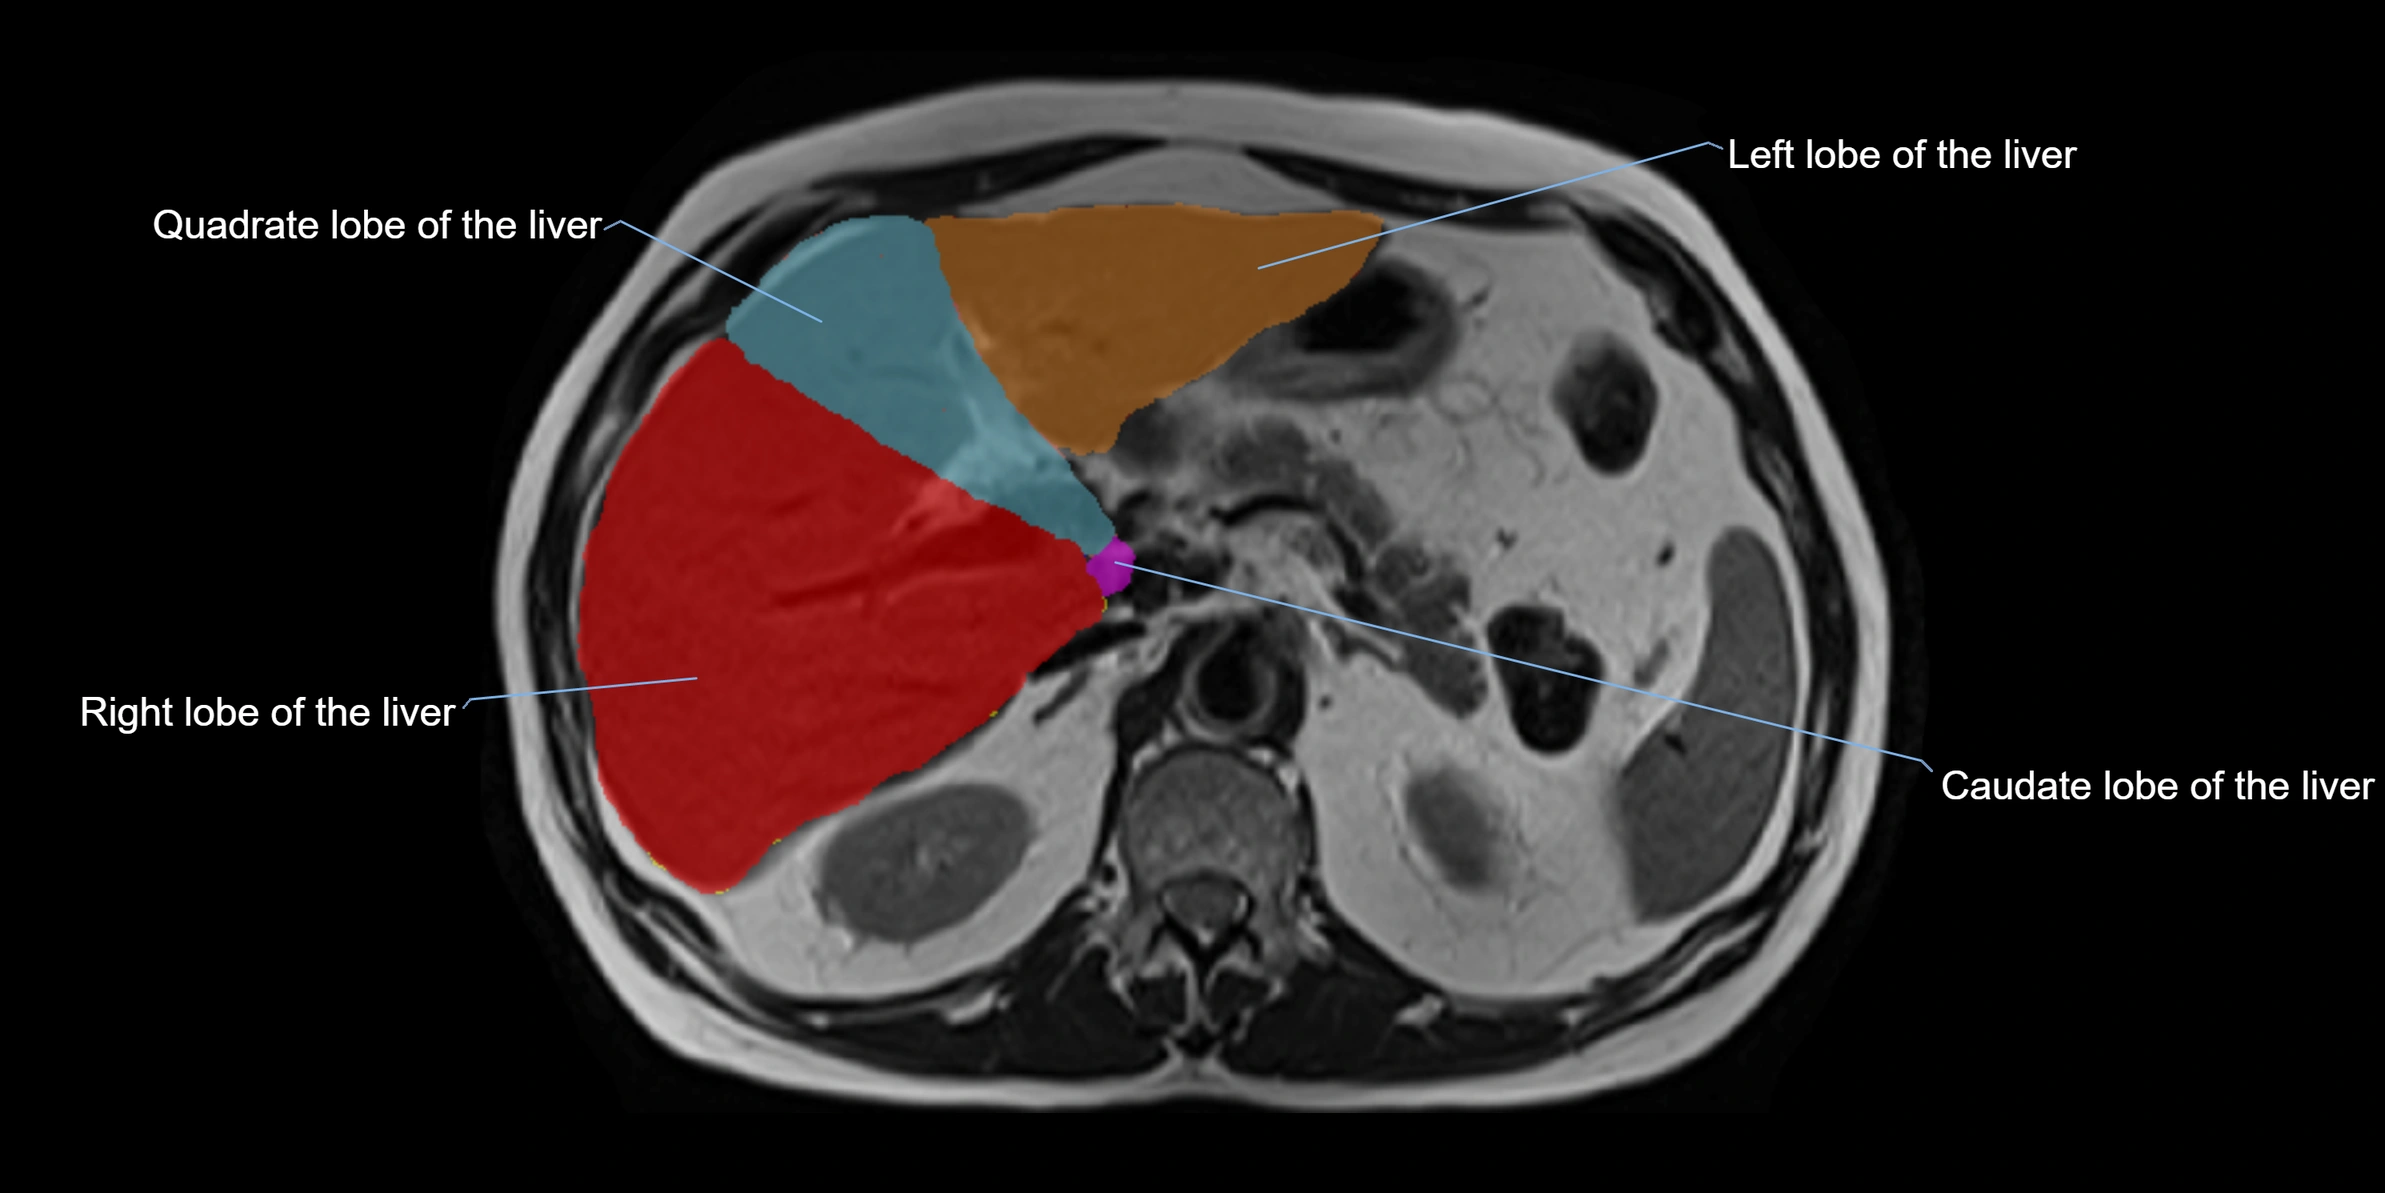

The caudate lobe of the liver is a distinct anatomical subdivision of the liver, designated as segment I in Couinaud’s classification. It lies on the posterior surface of the liver, between the fissure for the ligamentum venosum (left boundary) and the groove for the inferior vena cava (IVC) (right boundary). Superiorly, it is related to the posterior liver surface, and inferiorly it is separated from the left lobe by the porta hepatis.

The caudate lobe is unique because it receives dual portal venous and arterial inflow from both the right and left portal veins and hepatic arteries. It also has independent venous drainage directly into the IVC via multiple small hepatic veins, unlike other lobes that drain through the three main hepatic veins.

This anatomical autonomy makes the caudate lobe especially significant in liver surgery, transplantation, and hepatic venous outflow obstruction syndromes (e.g., Budd–Chiari syndrome). Enlargement of the caudate lobe is a characteristic imaging feature in chronic liver disease and cirrhosis.